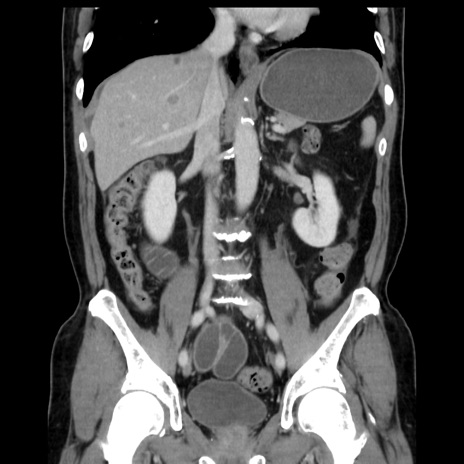

症例16(冠状断像)

【症例】 70歳代男性

【主訴】 腹痛、嘔吐

【現病歴】 約1ヶ月前より間欠的に腹痛と嘔吐あり、当院消化器内科を受診したところCTで多発する肝臓のLDAを指摘され、精査中であった。以降は消化器症状は安定していたが、2日前より嘔気と腹痛があり、同日より排便・排ガスが消失した。改善認めず、 本日、救急外来を受診した。